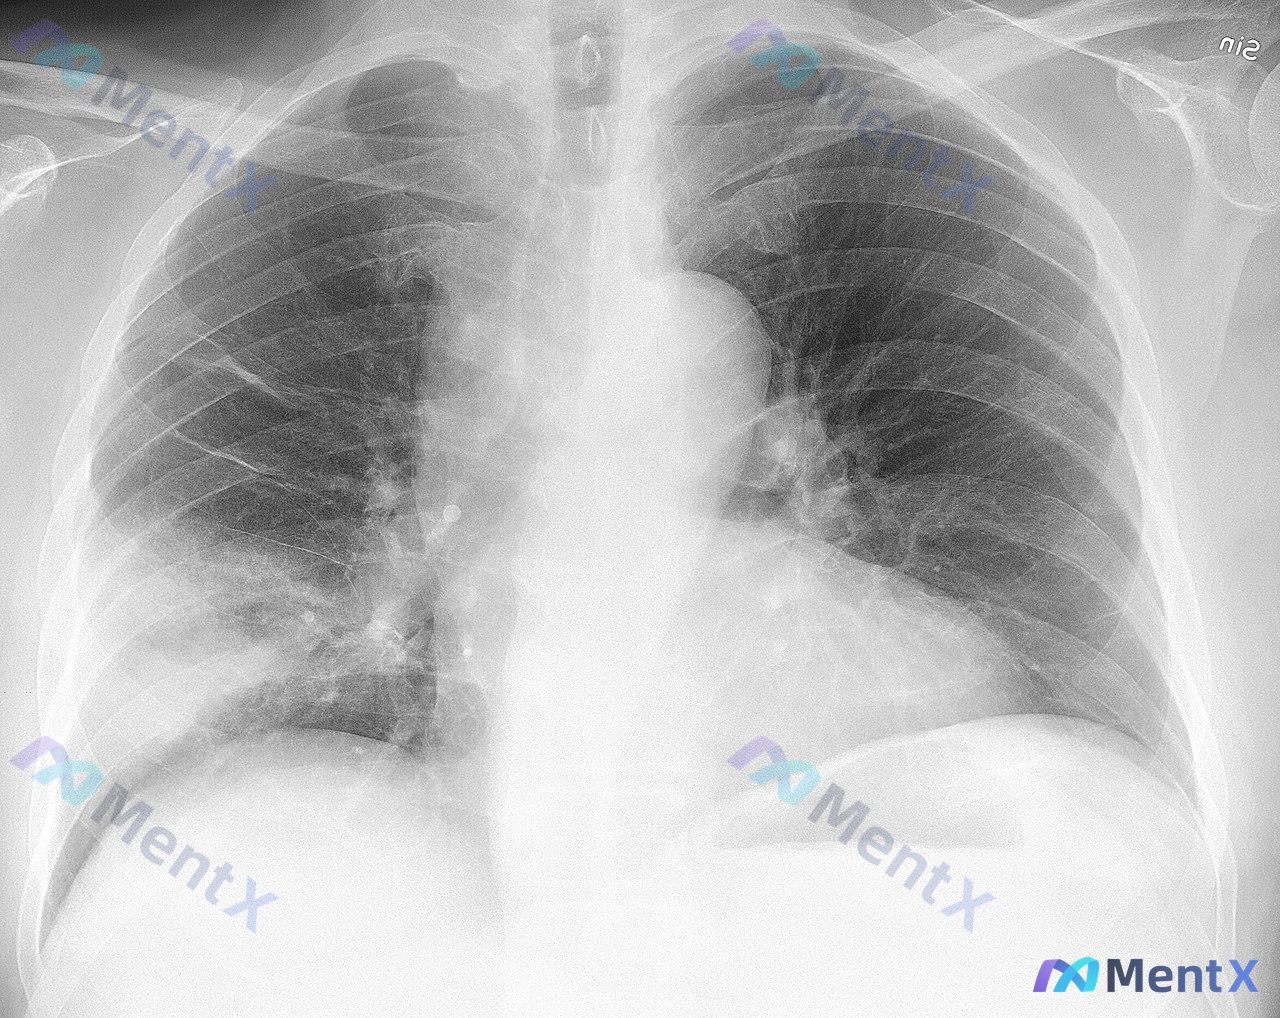

刚整理完一份很有参考意义的胸部CT读片病例,跟大家分享一下,整个分析思路挺值得梳理的。 一、病例影像基本信息 这是一张胸部CT肺窗横断面影像,问题是检出了「Airspace opacity(气腔不透明度)」,完整影像评估结果如下: 1. 胸廓对称,纵隔居中,双侧胸膜无明显积液积气,胸膜光滑 2. 右...

看到一张胸部CT肺窗横断面图像,整理了一下分析思路,和大家讨论。 病例资料: 患者的详细病史和其他检查结果未提供,仅提供了这张CT肺窗图像。 影像观察: 1. 扫描层面位于心室水平上方、肺门区域(主肺动脉分叉附近),可见升主动脉、降主动脉、主肺动脉及其分支、气管周围血管结构。 2. 双肺透亮度对称正...